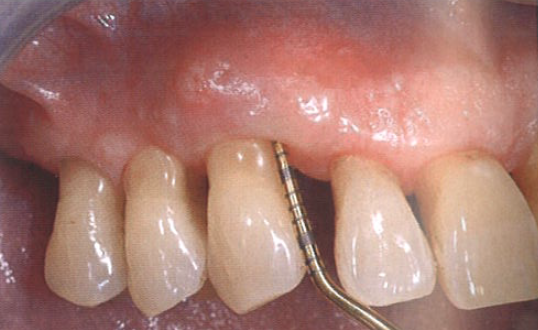

患者表示相比于手术治疗而言,更愿意进行激光辅助的非手术治疗(图9a)。

尖牙近中面的探诊深度大约为10 mm(图9b),相邻前磨牙近中面的探诊深度为7 mm。

图9  a为牙周激光辅助治疗;b为尖牙近中面的探诊深度深度,大约为10 mm